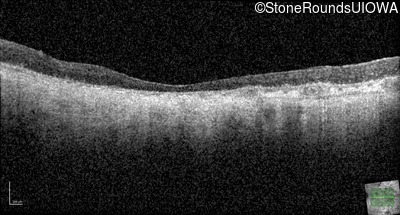

Optical Coherence Tomography - Left - Light Perception

Exemplar / OCT Stack